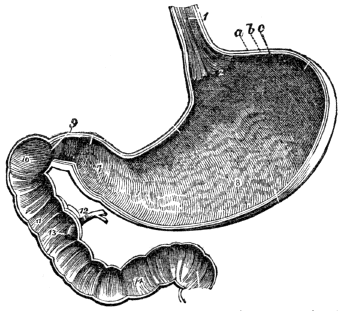

| 13. | Anatomy of the Digestive Organs, | 113 |

| 14. | Physiology of the Digestive Organs, | 124 |

| 15. | Hygiene of the Digestive Organs, | 129 |

| 16. | Hygiene of the Digestive Organs, continued, | 142 |